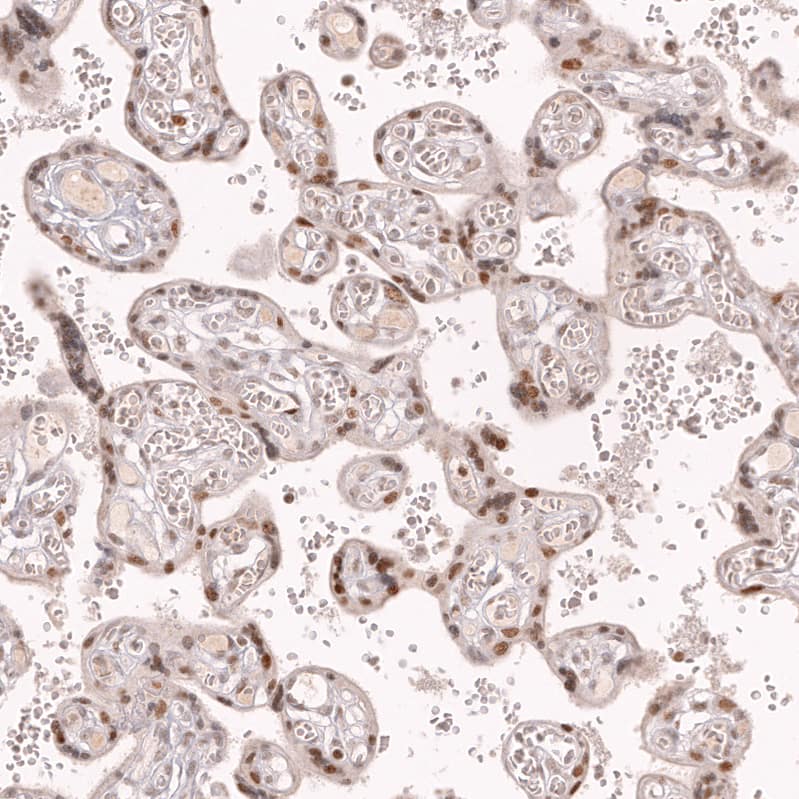

Staining of human placenta shows moderate nuclear positivity in trophoblastic cells.